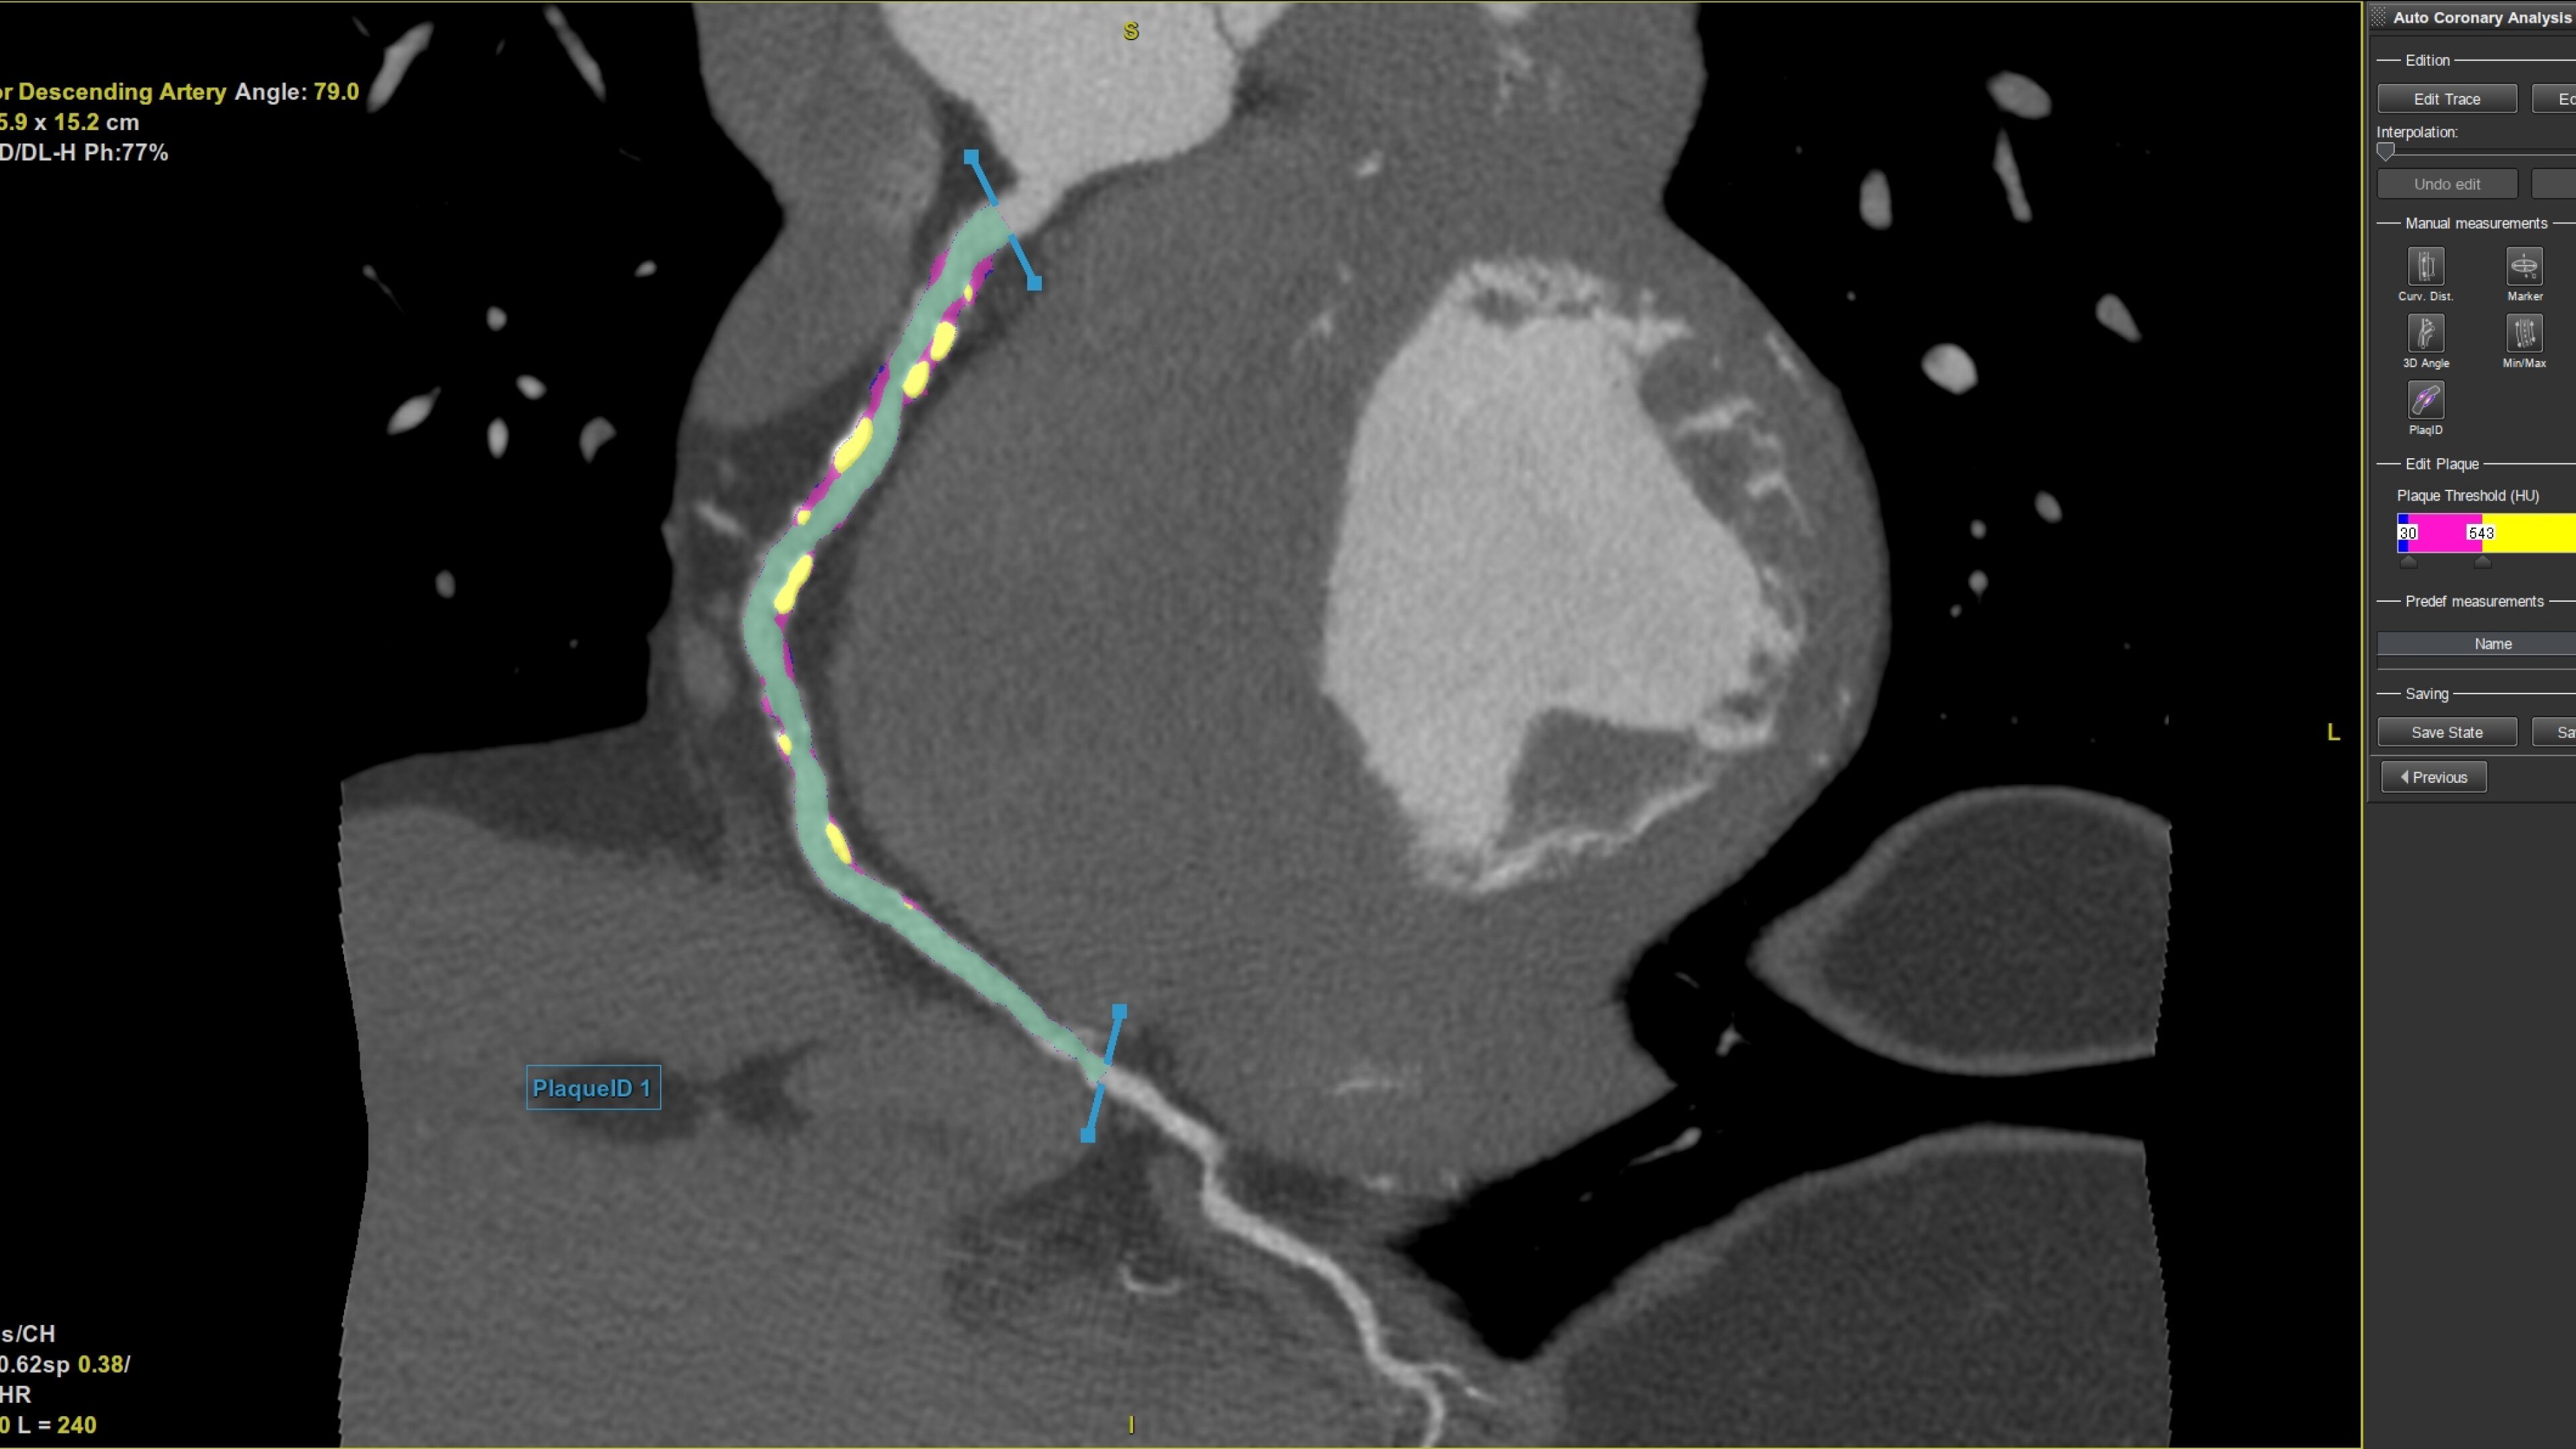

• Plaque ID provides volume measurements for four distinct Hounsfield ranges to aid with identification and visualization of coronary plaque

Plaque ID tool assists in visualizing and quantifying plaque burden